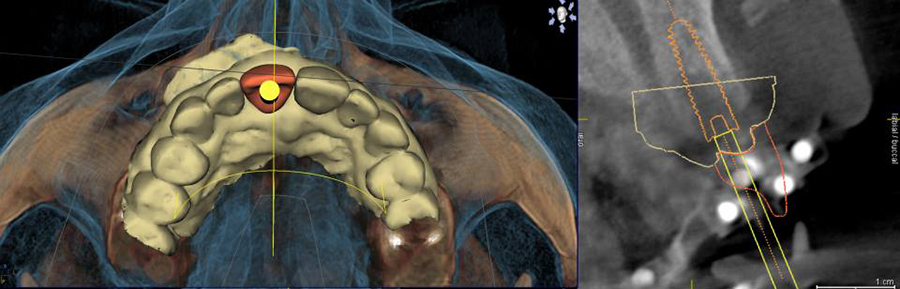

From the digital models, a surgical guide is fabricated by Sicat which has holes that exactly match our desired implant placement. The guides are placed in position during surgery. Using a special set of drills, the guide enables us to make the exact placements we have already planned within microns. Below are examples of computer-generated drill guides. There are various types of printed guides used for different situations.